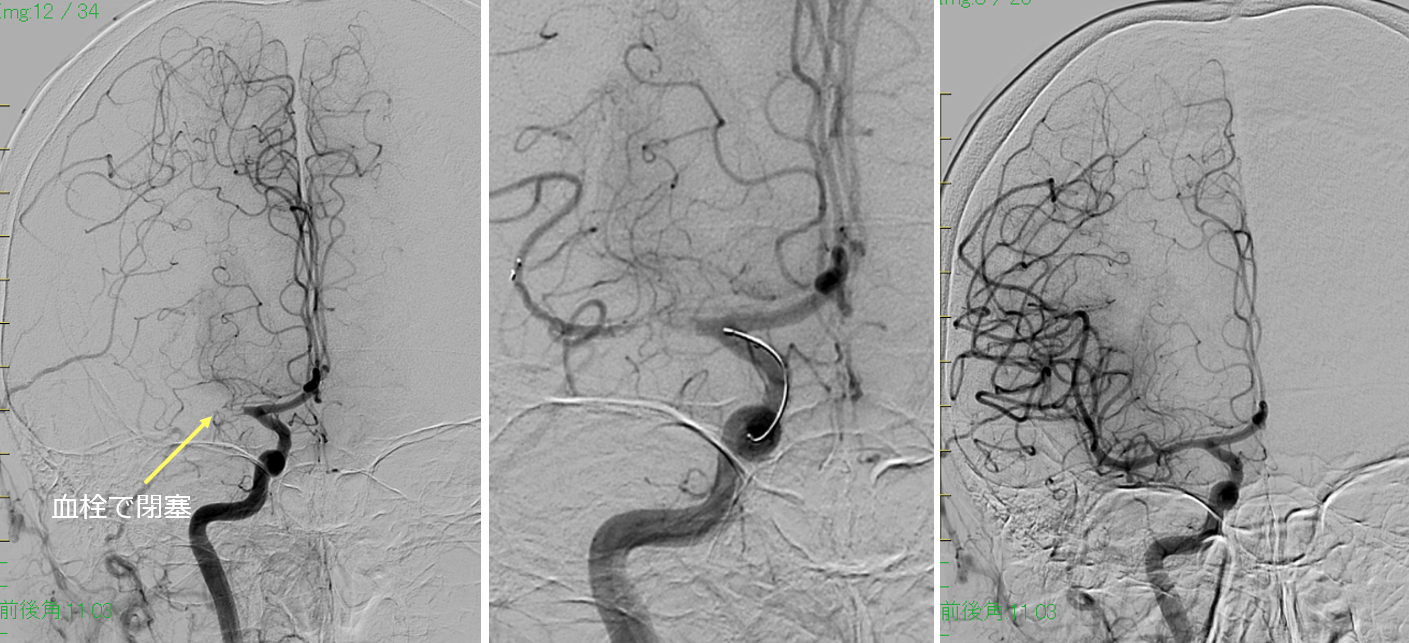

脳塞栓(右中大脳動脈塞栓)

治療前

ステント誘導

11分間で完全再開通